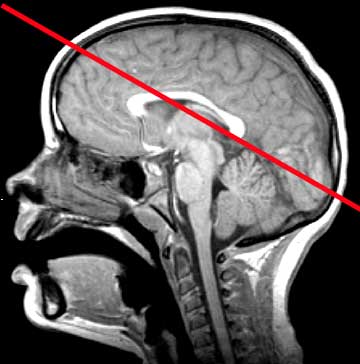

Normal Anatomy